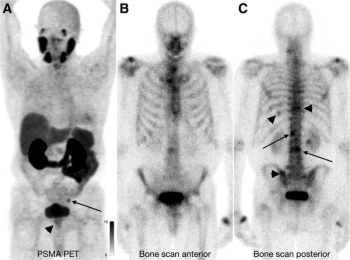

Fifty-seven percent of patients with prostate cancer diagnosed with osseous metastases on bone scans had negative findings on PSMA PET imaging, according to findings from an international multicenter comparative study.